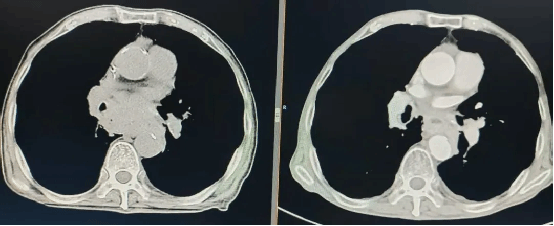

近日,身负十余种基础疾病、因重症肺炎诱发多器官功能不全(MODS)的90岁高龄患者朱老先生(化名)。在重症医学科(ICU)医护团队精准、高效的救治下成功脱险,现已病情... -